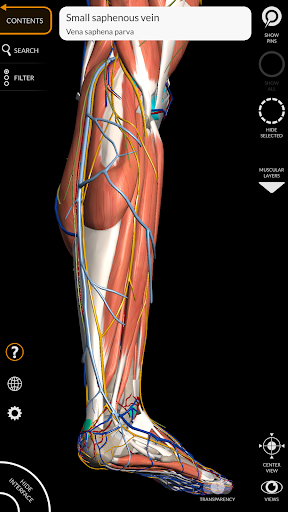

"Anatomía - Atlas 3D" permite estudiar la anatomía humana de forma fácil e interactiva.

A través de una interfaz sencilla e intuitiva es posible observar cada estructura anatómica desde cualquier ángulo.

Los modelos anatómicos 3D son especialmente detallados y con texturas de hasta una resolución de 4k.

La subdivisión por regiones y las vistas predefinidas facilitan la observación y el estudio de partes individuales o grupos de sistemas y las relaciones entre los diferentes órganos.

MODELOS ANATÓMICOS 3D

• Sistema musculoesquelético

nervioso • Sistema respiratorio • Sistema digestivo • Sistema urogenital (masculino y femenino) • Sistema endocrino • Sistema linfático • Sistema ocular y auditivo CARACTERÍSTICAS • Interfaz sencilla e intuitiva • Rotar y hacer zoom en cada modelo en el espacio 3D • Opción para ocultar o aislar uno o varios modelos seleccionados • Filtro para ocultar o mostrar cada sistema • Función de búsqueda para encontrar fácilmente cada parte anatómica • Función de marcador para guardar vistas personalizadas • Rotación inteligente que mueve el centro de rotación automáticamente • Función de transparencia • Visualización de músculos a través de niveles de capas desde las superficiales hasta las más profundas • Al seleccionar un modelo o un pin, aparece el término anatómico relacionado • Descripción de los músculos: origen, inserción, inervación y acción • Mostrar/ocultar interfaz de usuario (muy útil con pantallas pequeñas) MULTILINGÜE • Los términos anatómicos y la interfaz de usuario están disponibles en 11 idiomas: latín, inglés, francés, alemán, italiano, portugués, turco, ruso, español, Chino, japonés y coreano • Los términos anatómicos se pueden mostrar en dos idiomas simultáneamente REQUISITOS DEL SISTEMA • Android 8.0 o posterior, dispositivos con al menos 3 GB de RAM Reversi